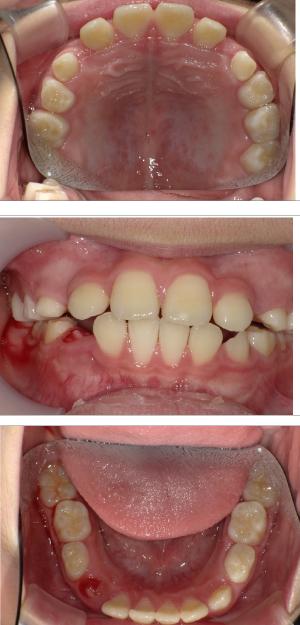

バイオブロック矯正(顎顔面口腔育成治療)

矯正治療は大人になって始めるよりも子どもの頃から始めた方が確実に良い結果をもたらします。成長が盛んな子供の時期に、顎や顔の成長を利用しながら治療ができる大きなメリットがあるからです。当院では、非抜歯矯正を推奨しておりバイオブロック矯正を取り入れています。

バイオブロック矯正の考え方は歯並びが悪くなる原因にアプローチする治療法になります。

舌の位置や口呼吸から乱れてしまった下顎の後退を正し、顎顔面が本来あるべき位置へと誘導させていく治療です。

- 歯並びの改善

- 歯を動かすのではなく顎の成長を促す

- 非抜歯矯正ができる

- 側方拡大だけでなく前方成長も促す

- お顔の成長が正しく美しく導くことができる